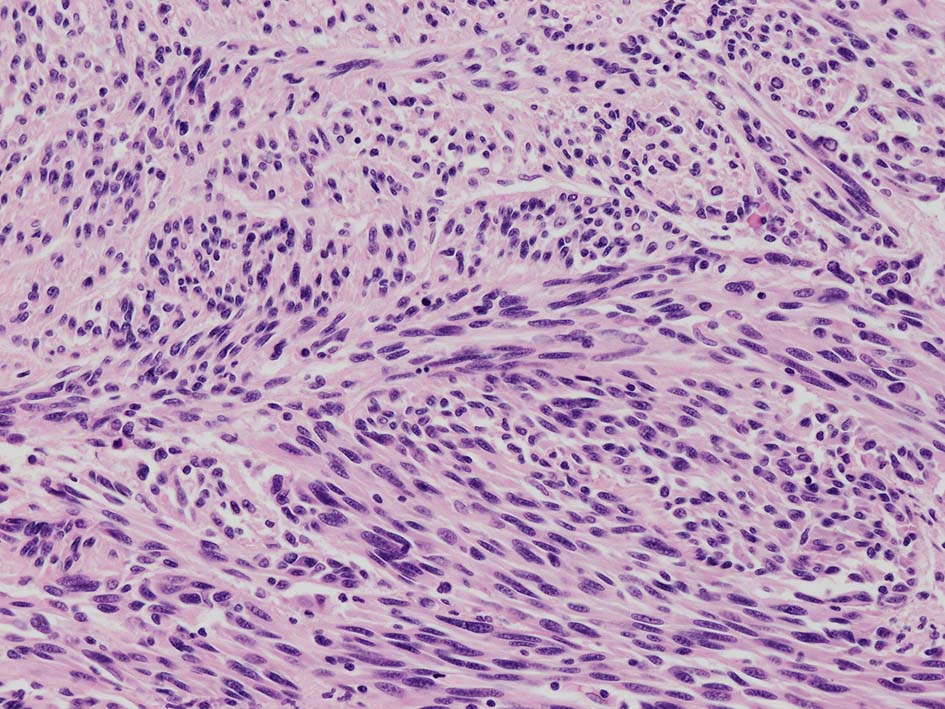

紡錘形異型メラノサイトが著明な間質反応(desmoplasia)を伴い増殖する特殊な色素性病変。*1. desmoplastic neurotropic melanomaは, desmoplastic melanomaのうち神経向性(neurotropism:神経周囲侵襲像)がめだつものでReedら*2が最初に報告した。

いずれも腫瘍細胞の異型性が乏しく, 背景の間質反応がめだつこと, メラニンの存在が目立たないことが特徴である。

病理組織所見*4

再発腫瘤病変の組織像